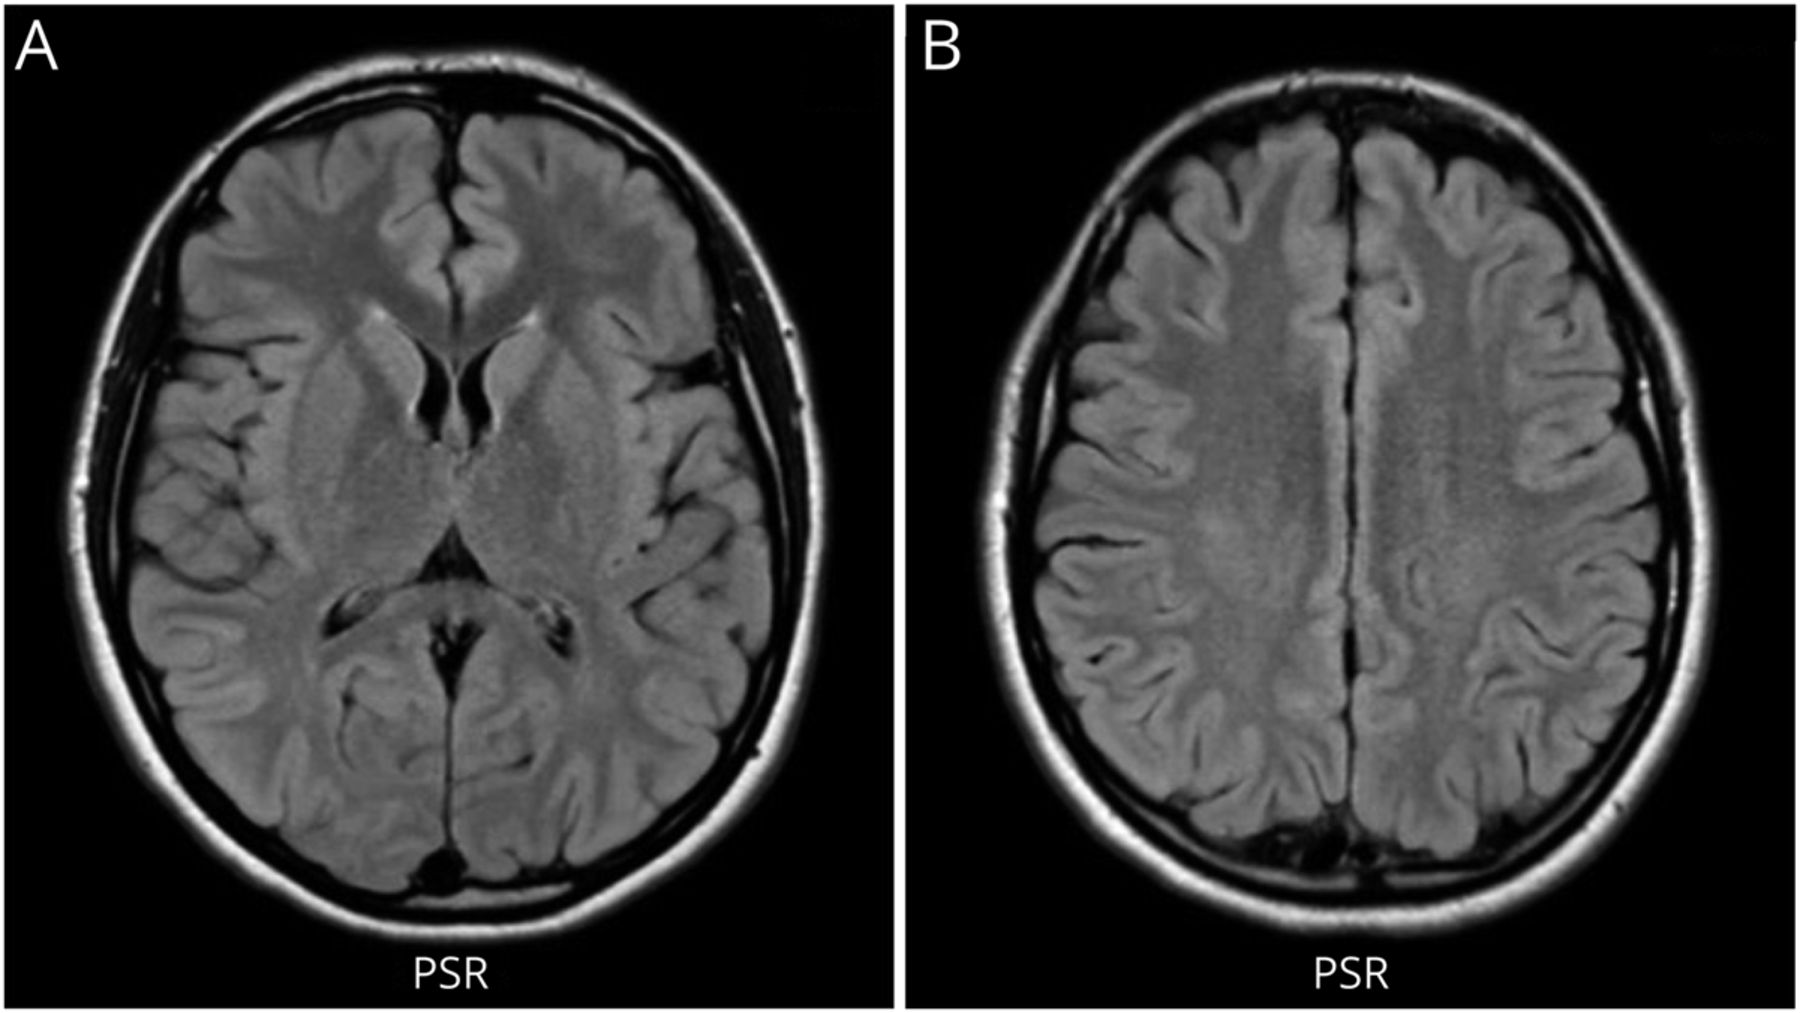

她最初看的是一位神经学家。当时的检查显示认知正常,颅神经完整,眼底正常,上肢力量正常。她的下肢弥漫性无力,全身力量为4/5。上肢反射正常,双侧髌骨有反射,双侧踝关节有阵挛。她的感觉检查显示双侧腿部振动感和本体感觉下降。温度和针刺感幸免。步态宽,需要助行器行走。颈椎和胸椎MRI显示从C5延伸至T11的脊背纵行广泛的T2高强度(图1).肌电图显示多处肌切面出现主动去神经。她的大脑核磁共振成像(图2)和实验室检查结果均不显著,包括正常的维生素B12 (625 pg/mL,参考范围232 - 1245 pg/mL),水通道蛋白4 (AQP4 Ab)阴性,髓鞘少突胶质细胞糖蛋白(抗MOG Ab)抗体阴性。此时未检测MMA和同型半胱氨酸。